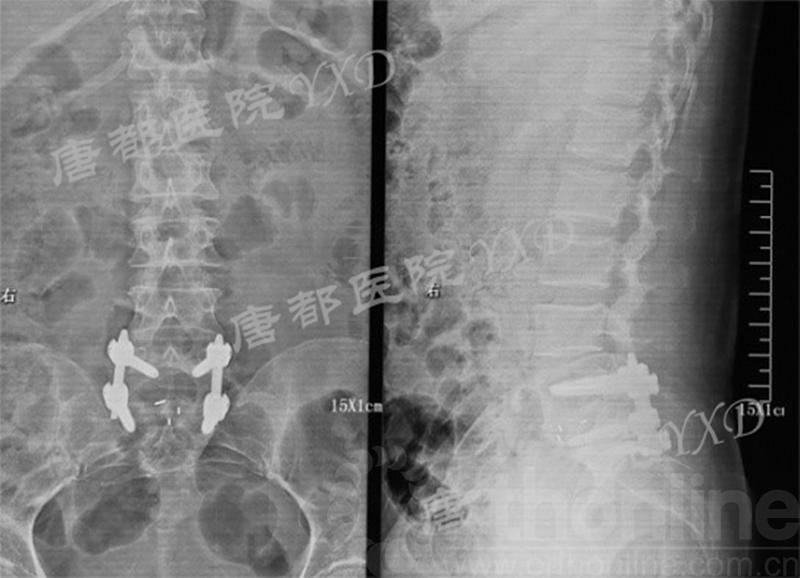

影像学检查:

诊断:腰椎间盘突出症术后复发

手术方案:显微镜辅助MI-TLIF腰椎翻修术

术中视频:http://api.orthonline.com.cn/attach/Case2.mp4(术中发现因前三次侧路及后路内镜手术的操作,术区大量瘢痕组织增生、与神经粘连严重;此外,摘除头侧游离髓核时连接有软骨终板脱落;在显微镜操作下,安全地将神经进行充分松解,压迫神经的游离髓核及软骨终板彻底清除。无手术并发症)